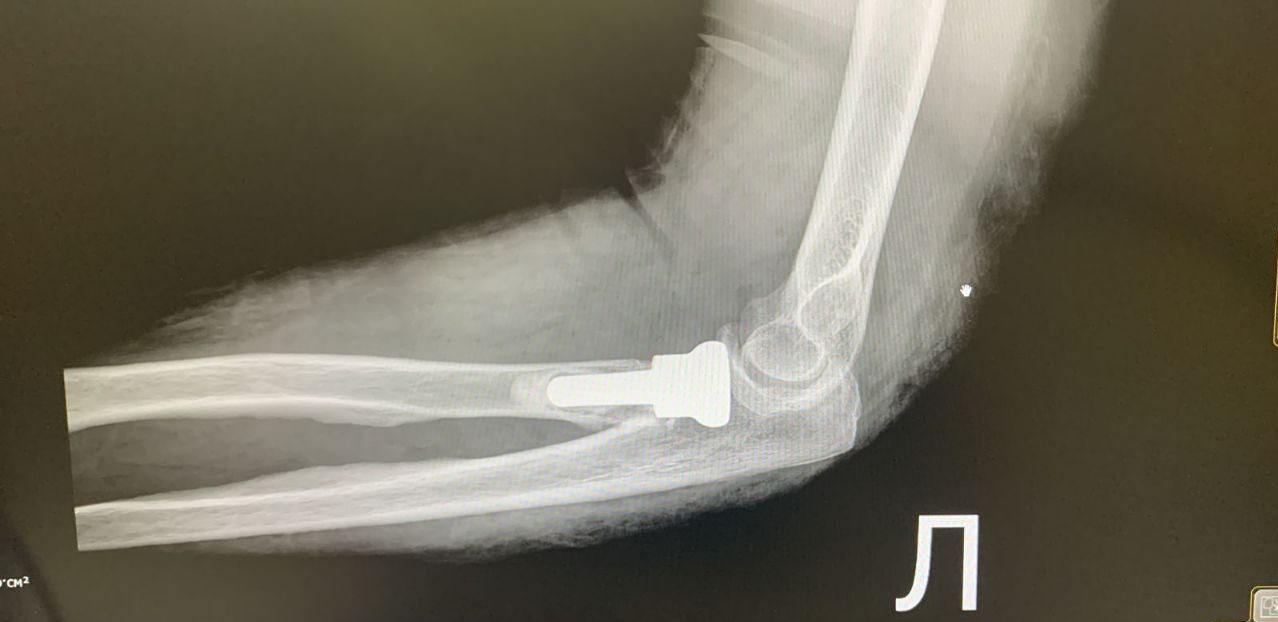

У первой пациентки — 66-летней женщины — был диагностирован оскольчатый перелом головки лучевой кости. У второго — 55-летнего мужчины — дистальный перелом метаэпифиза левой лучевой кости, перелом локтевой кости в верхней трети и оскольчатый перелом головки лучевой кости. Обе травмы были получены в результате неудачного падения.

— При таких травмах крайне сложно выполнить стабилизацию перелома с помощью пластин — так называемый остеосинтез. Поэтому было принято решение провести протезирование головки лучевой кости — вмешательство, требующее высокой точности и опыта врачей. Во время операции удаляются костные осколки, формируется специальное ложе в проксимальном отделе лучевой кости, после чего в него устанавливается эндопротез головки лучевой кости, — рассказал заведующий травматологическим отделением Тавриз Аббасов.

Главное преимущество этой методики — возможность в кратчайшие сроки восстановить полную функцию локтевого сустава. После операции пациенты смогут без ограничений сгибать, разгибать и вращать руку.